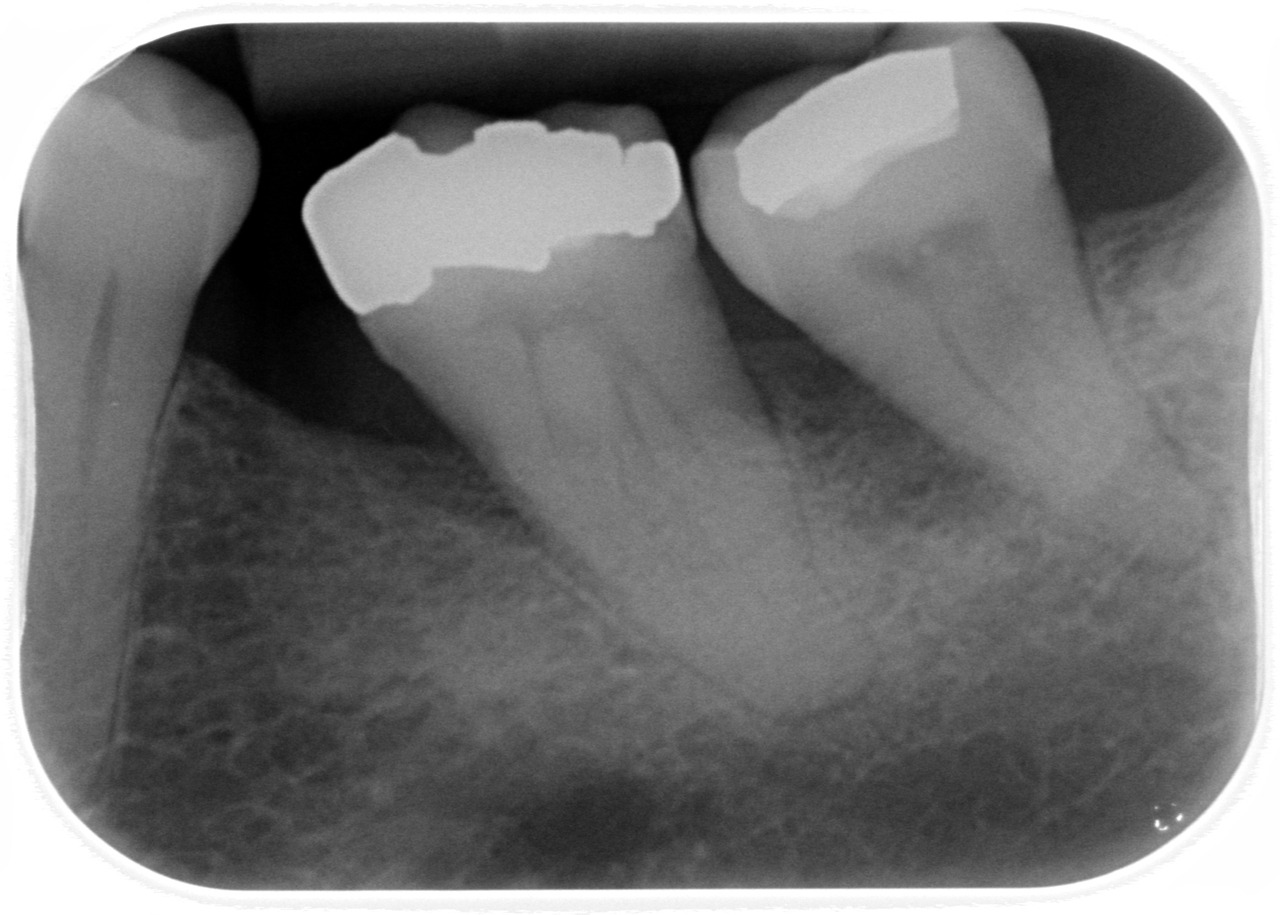

Good teeth, bad teeth

I first went to the dentist way back in the early 50s when dental practice was fairly primitive: needles seemed blunt, fillings took an age to cure, loud scary drills driven by string ran hot and even though Xrays would have existed they weren’t in common use. It seemed like the practice of dentistry had…